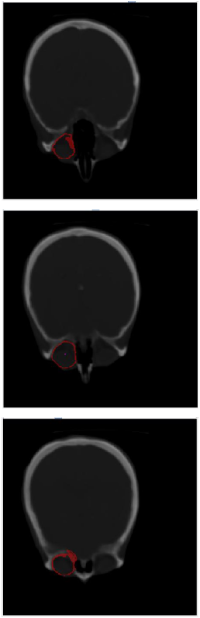

Solche Segmentierungsalgorithmen trennen relevante von irrelevanten Daten und erkennen Bildinhalte, die unter bestimmten Homogenitätskriterien inhaltlich zusammen gehören. Solche Verfahren sollen robust gegenüber Bildstörungen sein und der Genauigkeit einer manuellen Segmentation zumindest ebenbürtig sein.

Ziel dieser Arbeit ist es, zwei Verfahren zu implementieren und zu untersuchen, die zur Segmentierung aktive Konturen (oder Snakes) verwenden und auf Level-Set Methoden aufbauen. Das erste Verfahren nutzt das so genannte Edge-stopping, wohingegen das zweite Verfahren auf einem Energy Minimization Algorithmus basiert.